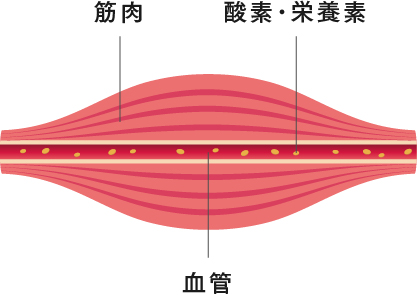

コリ・痛みの

発生原因

発生原因

健康な筋肉

筋肉が柔らかく、血管が広がっていて血行も良好な状態。

コリの発生した筋肉

筋肉が硬くなり、血管を圧迫。血行不良にになると、脳がコリを認識。